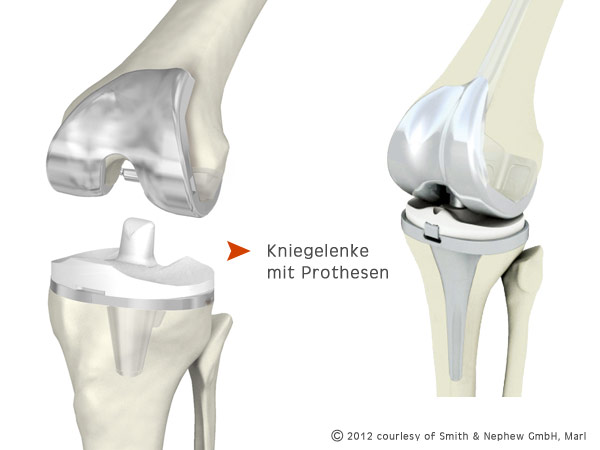

Nach dem Eröffnen des Gelenks bereitet Ihr Operateur die Ober- und Unterschenkelknochen für die Befestigung der Implantate vor und beginnt mit der Implantation der Prothesen.

Bewährt haben sich hier unter anderem das Einsetzen mit einem speziellen Knochenzement oder das zementfreie Einpressen der Prothese in den Knochen. Welches die ideale Methode ist, hängt von der Art Ihrer Prothese ab und wird von Ihrem Arzt festgelegt.

Möglicherweise ist für Ihren Fall ein Kniescheibenimplantat notwendig. Es wird nach der kompletten Implantation der Knochenprothesen an der Rückseite Ihrer natürlichen Kniescheibe fixiert.